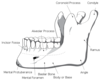

What bones can be seen from the lateral aspect of the skull?

- frontal

- parietal

- temporal

- temporalis process of zygomatic bone

- sphenoid bone

- occipital bone

- mandible

- maxilla

What parts of the temporal bone can be seen when viewing the skull laterally?

a. squamous part - zygomatic process

b. tympanic part - external auditory meatus

c. mastoid process

What part of the spenoid bone can be seen when viewing laterally?

a. greater wing (probably lateral plate as well)